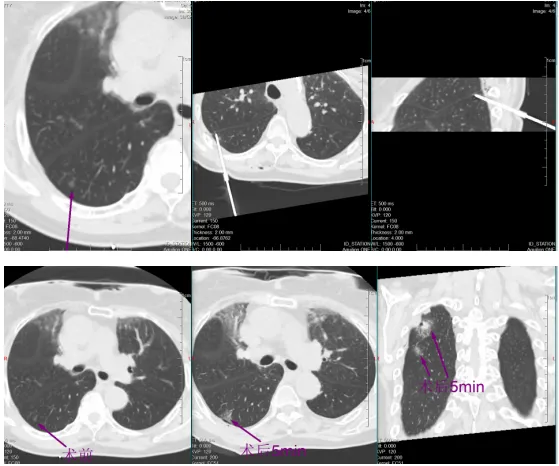

稍后,于明川与冯文汉等团队成员密切配合,向难度更高的第二枚结节发起冲击。这枚结节藏在叶间裂与胸膜构成的狭小夹角内,可操作空间极小,如同在“夹缝中绣花”。按照术前预案,于明川放弃平行进针思路,采用由下而上的特殊进针方式,巧妙避开关键解剖结构。针尖精准抵达结节区域,经过反复测量确认安全后,30瓦功率持续消融一分钟。术中,黄女士的心率、血压始终平稳,未出现任何不良反应。术后CT扫描证实,结节被完全覆盖,烧灼区与叶间裂仅隔几毫米,这毫厘之间的精准,正是生命安全的坚实屏障。

一小时后,铅门再次打开。于明川将黄女士的儿女引至屏幕前,影像清晰地显示:两枚结节已被完全覆盖,消融范围边缘距离关键解剖结构仅存毫厘之差。“两个结节都顺利消融成功了,没有并发症,手术很成功!” 话音落下,黄女士儿女心中悬了许久的大石终于落地。看着术后安然躺在病床上、面容平和的母亲,他们眼中盈满欣慰。